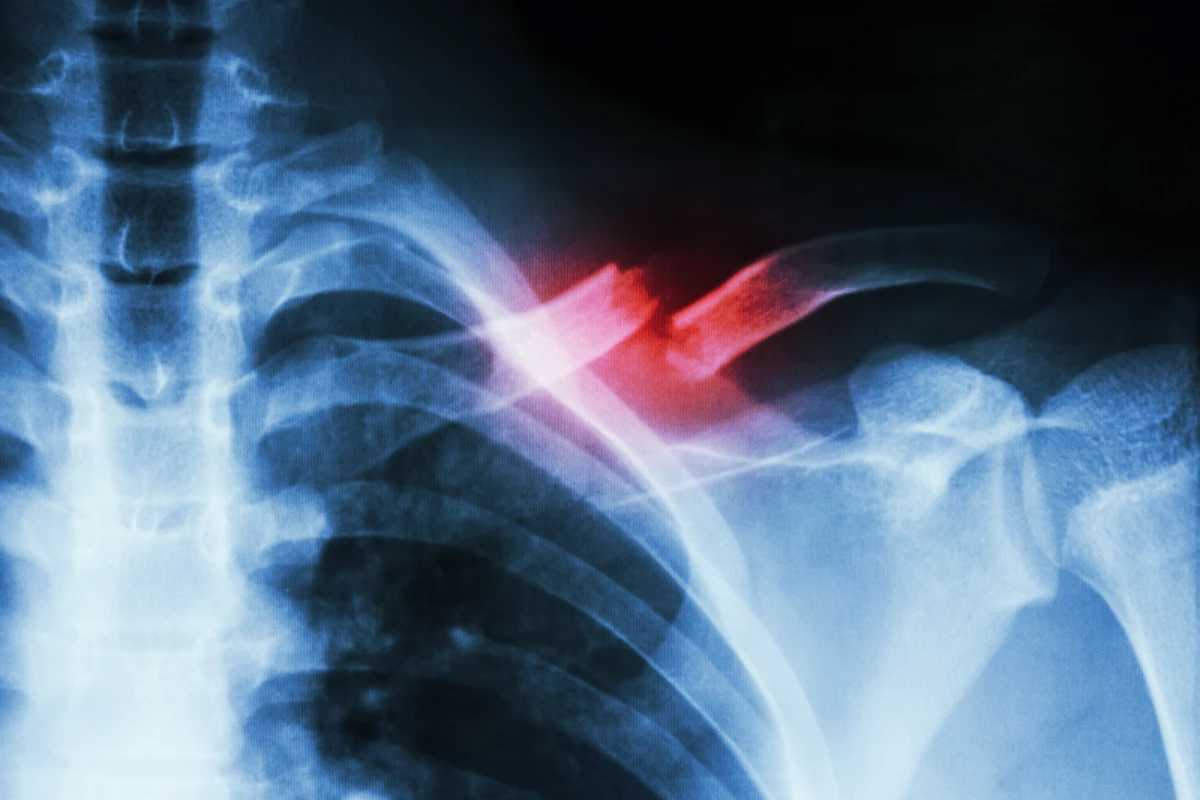

In rat experiments the duo of drugs increased levels of circulating stem cells and sped up healing of a spinal fracture

A new proof-of-concept study has found a combination of two drugs, already approved by the FDA for other uses, may boost the release of stem cells from bone marrow and accelerate the healing of broken bones. Only demonstrated in animals at this stage, the researchers suggest clinical trials could progress rapidly considering the drugs have already been demonstrated as safe in humans.

The new research set out to investigate whether any currently approved drugs can function to mobilize the body’s natural ability in releasing MSCs, with a view on speeding up healing of bone fractures. A study published in the journal npj Regenerative Medicine, describes the testing of two already approved drugs in a rodent spinal injury model.

The results suggest the duo of drugs mobilize MSCs into the bloodstream and speed up the process of bone formation and healing by enhancing the binding of calcium to the injury site. Tariq Fellous, first author on the new study, suggests the next step is to investigate whether this drug combination enhances blood MSC levels in human subjects.